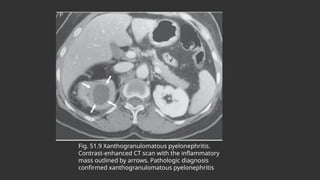

XANTHOGRANULOMATOUS PYELONEPHRITIS

 Is a poorly understood granulomatous inflammation of renal parenchyma associated with

obstruction and infection of the urinary tract

 The renal parenchyma is replaced with a diffuse or segmental cellular infiltrate of foam cells,

which are lipid-laden macrophages, which may extend beyond the renal capsule to the

retroperitoneum

 Its pathogenesis appears to be multifactorial, with infection complicating obstruction and leading

to ischemia, tissue destruction, and accumulation of lipid deposits.

 Typical pts are middle-aged women and have chronic symptoms such as flank pain, fever, chills,

and malaise.

 Flank tenderness, a palpable mass, and irritative voiding symptoms are common.

 The urine culture is usually positive with E. coli, other gram-negative bacilli, or S. aureus.

 CT generally shows an enlarged nonfunctioning kidney, often the presence of calculi and low-

density masses (xanthomatous tissue), maybe difficult to distinguish from neoplastic disease.

 Broad-spectrum antimicrobials are indicated, but total or partial nephrectomy is usually

necessary for cure

Fig. 51.9 Xanthogranulomatous pyelonephritis.

Contrast-enhanced CT scan with the inflammatory

mass outlined by arrows. Pathologic diagnosis

confirmed xanthogranulomatous pyelonephritis